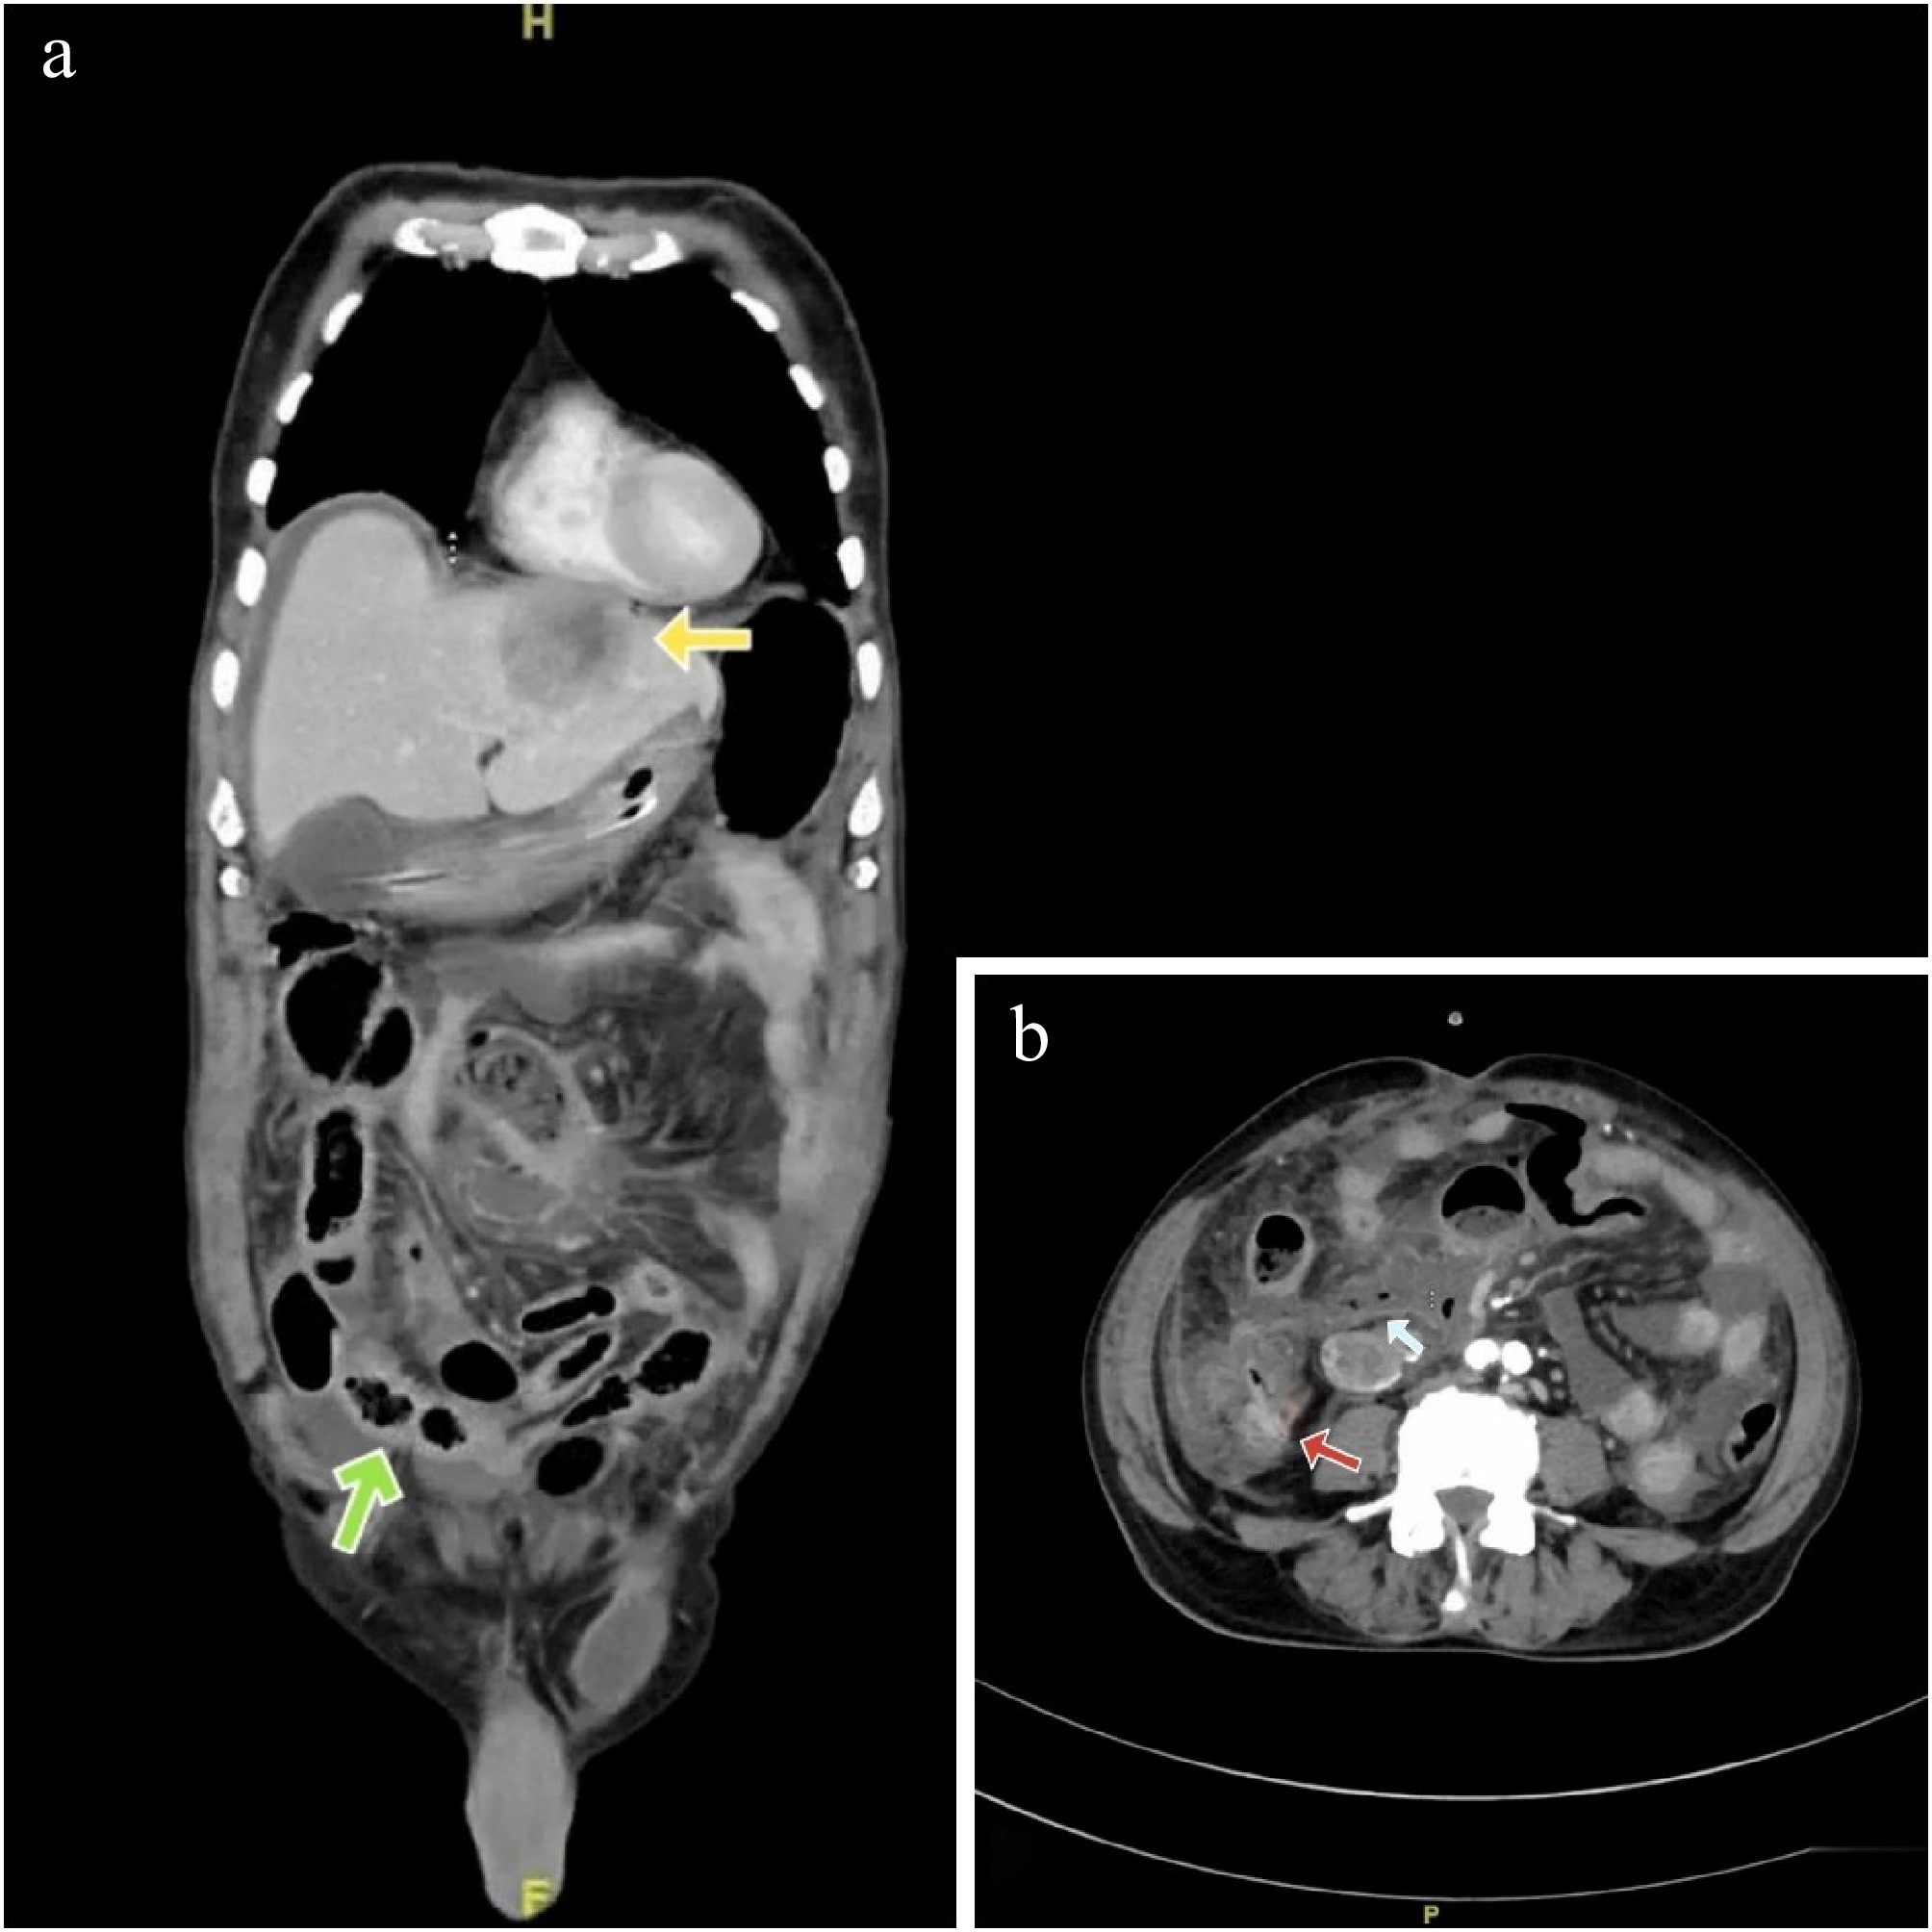

Intravenous contrast CT of abdomen showed an irregular asymmetric hyper-enhancing circumferential wall thickening seen in the terminal ileum and ileo-cecal junction for a length of 4.5 cm (Fig. 1a) with a focal wall defect in the anterior wall of terminal ileum and extraluminal air foci suggestive of perforation (Fig. 1b). Moderate ascites with diffuse mesenteric and omental fat stranding was also seen. Multiple hyper-enhancing enlarged nodes along the right ileo-colic vessels and a well-defined irregular heterogeneously enhancing lesion with central non-enhancing areas and peripherally enhancing solid components measuring 5 cm seen in segments 2 and 3 of the liver in the arterial phase, likely metastatic with central necrosis, was reported (Fig. 1a).

Figure 1.

(a) Yellow arrow - heterogenous, peripherally enhancing lesion in segments 2, 3 of liver (Hounsfield units: min- 10, max- 120, avg- 84). Green arrow - hyperenhancing circumferential thickening of the terminal ileum and ileo-caecal junction (Hounsfield units: min- 15, max- 100, avg- 60). (b) Red arrow showing thickened enhancing wall of ileo-caecal junction and a light blue arrow showing extraluminal gas pockets (Hounsfield units: min- 600, max- 1000, avg- 890).